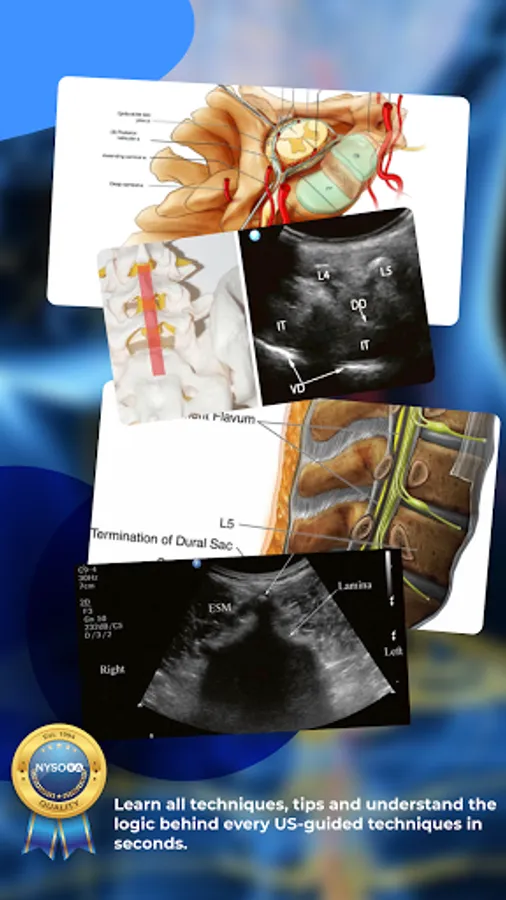

Published by the world’s leading authority on ultrasound, Dr. Samer Narouze. NYSORA Ultrasound-Guided Pain Blocks App describes the most practical and applicable techniques of ultrasound-guided pain medicine.

Clear images, illustrations, ultrasound images, functional anatomy, and ultrasound-guided pain and MSK procedures;

Ultrasound-guided: facet injections, median branch blocks, lumbar root injections, sacroiliac injection, celiac plexus block injection, blocks for pelvic pain, sympathetic block, stellate ganglion block, joint and bursa injections, knee injections, ultrasound-guided cervical discography, elbow, and shoulder bursa injections.